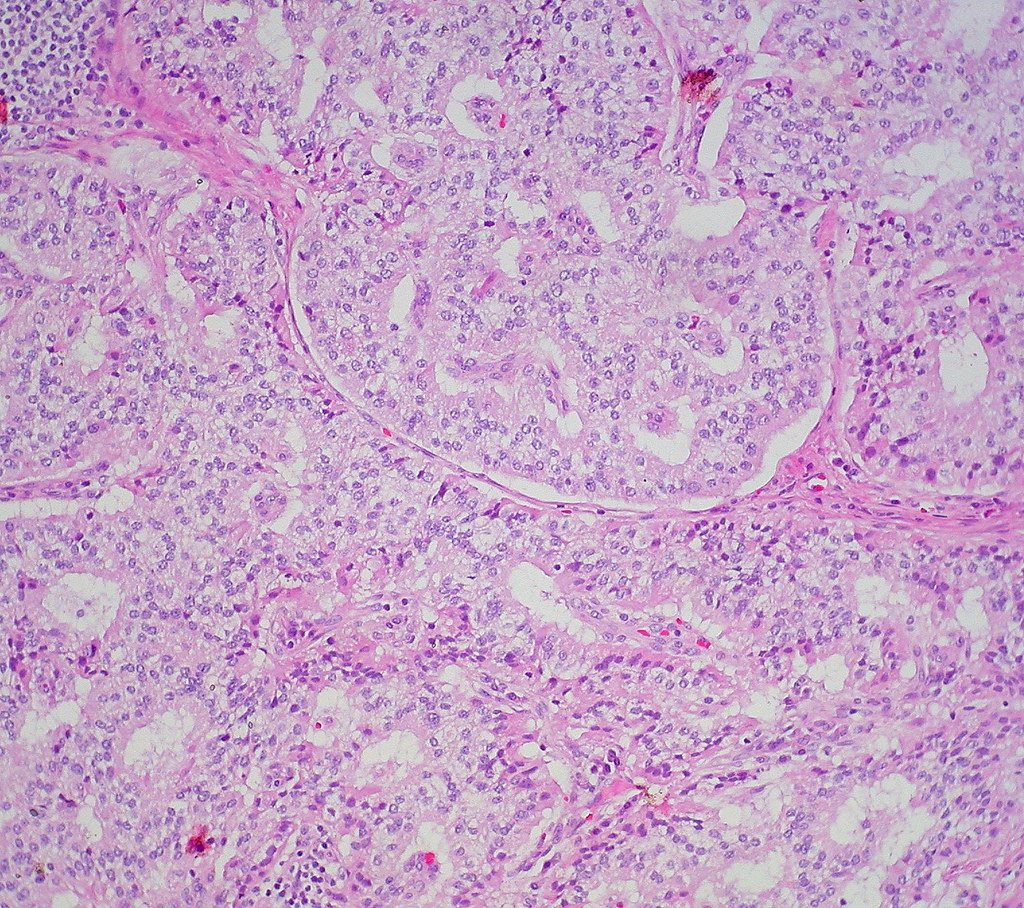

Welldifferentiated neuroendocrine tumor of the duodenum Flickr

Welldifferentiated neuroendocrine tumor of the duodenum Flickr Neuroendocrine Cancer Duodenum Neuroendocrine tumors in the small intestine (duodenum, jejunum, and ileum), colon, and rectum sometimes cause signs or symptoms as. Neuroendocrine tumors are cancers that begin in specialized cells called neuroendocrine cells. Neuroendocrine cells have traits similar to. Upper gastrointestinal neuroendocrine tumors (nets) are rare tumors which are increasingly recognised by practising. Neuroendocrine neoplasms originating from the gut are increasingly diagnosed. Neuroendocrine Cancer Duodenum.

Welldifferentiated neuroendocrine tumor of the duodenum Flickr Neuroendocrine Cancer Duodenum Neuroendocrine cells have traits similar to. Neuroendocrine neoplasms originating from the gut are increasingly diagnosed as a result of the rise in radiological and endoscopic procedures, improved pathological classification, and. Neuroendocrine tumors are cancers that begin in specialized cells called neuroendocrine cells. Upper gastrointestinal neuroendocrine tumors (nets) are rare tumors which are increasingly recognised by practising. Neuroendocrine tumors in the. Neuroendocrine Cancer Duodenum.

Welldifferentiated neuroendocrine tumor of the duodenum Flickr Photo Sharing! Neuroendocrine Cancer Duodenum Neuroendocrine tumors in the small intestine (duodenum, jejunum, and ileum), colon, and rectum sometimes cause signs or symptoms as. Neuroendocrine neoplasms originating from the gut are increasingly diagnosed as a result of the rise in radiological and endoscopic procedures, improved pathological classification, and. Neuroendocrine tumors are cancers that begin in specialized cells called neuroendocrine cells. Upper gastrointestinal neuroendocrine tumors (nets). Neuroendocrine Cancer Duodenum.